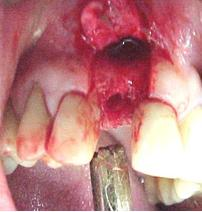

Paciente número 0283, de 46 anos de idade. Chegou à clínica com um abscesso

no dente 12. Queixava de muita dor e desconforto.

No exame clínico pode-se ver que havia grande mobilidade da coroa, estava

praticamente solta.

O exame radiográfico mostrou uma pequena linha de fratura. Foi indicada a extração do dente.

A paciente ficou muito abalada em ficar sem o dente, por questões estéticas. Foi proposta uma PPR ou mesmo um dente ser colado no lugar, o que deixou a paciente insegura.

Propusemos a colocação de um implante lançado pela Conexão, o Conect, que permite a colocação imediata de uma coroa estética no implante colocado, não sendo necessário para isso a espera de 6 meses para a osseointegração.

Prontamente a paciente achou excelente idéia, indicando a colocação de implante Conect.

Figura n°1. Caso clínico: Paciente de 46 anos de idade, já portadora de 4 implantes, colocados há 6 anos, compareceu ao consultório após a perda da coroa do dente 12 com fratura da raiz.

Figura n°2. A análise radiográfica, mostrou uma raiz com muito pouca implantação, reação apical e ao exame clínico uma provável linha de fratura, transversal, alterando o ligamento periodontal no terço médio da raiz. Assim a raiz foi condenada, e indicado à paciente um implante imediato. Na radiografia pode-se observar outras alterações nos ápices dos dentes 13 e 14.

Figura n°3. Esta é a fotografia antes da cirurgia para implante. A imagem não ficou boa, mas pode-se notar com atenção uma linha de fratura iniciando na região vestibular com direção à distal.

Antes de ser realizada a cirurgia, a paciente foi moldada, feito modelo de estudo para confecção de uma coroa provisória e do guia cirúrgico. Os detalhes protéticos serão discutidos no final da parte cirúrgica.

Antes da cirurgia a paciente foi submetida uma anti-sepsia bucal com bochechos de Periogard seguido de uma ampla profilaxia com o jato de bicarbonato de sódio.

Figura n°4. Esta fotografia mostra a incisão inicial, intra-sulcular, com lâmina N15, para melhor aproveitamento do tecido mole na reconstrução da gengiva marginal do implante. O retalho deve sempre ser total, ou seja, muco-perióstico.